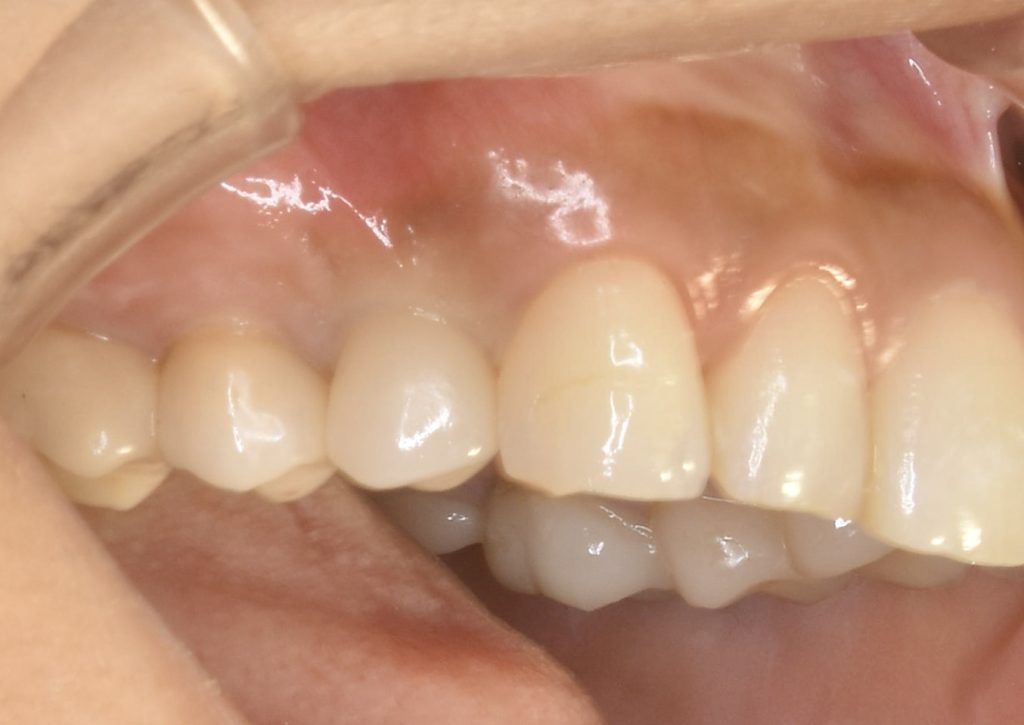

神経がないので痛みというより違和感程度でしたが、抜歯に同意していただき、抜歯と同時にインプラント治療を行い、できるだけ負担を減らし治療期間を短縮する計画を立てました。

この症例にかかる治療期間 約4ヶ月

この症例にかかる費用 約63万円(税別)